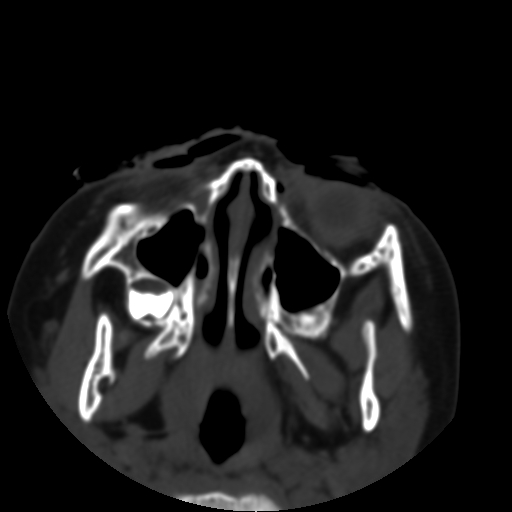

以下是引用深泽交通医院在2009-10-16 8:25:00的发言:[br]右眼环出血伴异物

以下是引用卜一在2009-10-16 15:01:00的发言:[br]右眼球挫裂伤伴异物!

以下是引用拾荒者在2009-10-17 18:38:00的发言:[br]鼻面部皮下积气,右侧睑缘及眼球壁高密度异物影,左侧眼球壁晶状体内侧缘处是圆形低密度影。低密度异物?应提请眼科医生注意。